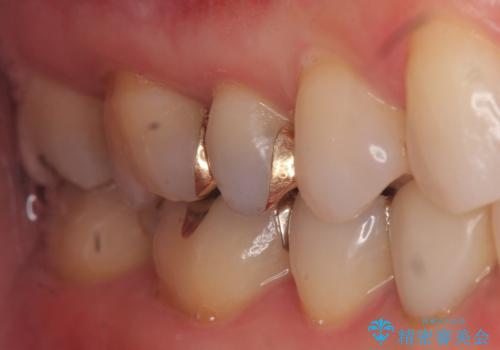

口を開けた時、銀歯が目立たなくなり、大変満足して頂けました。